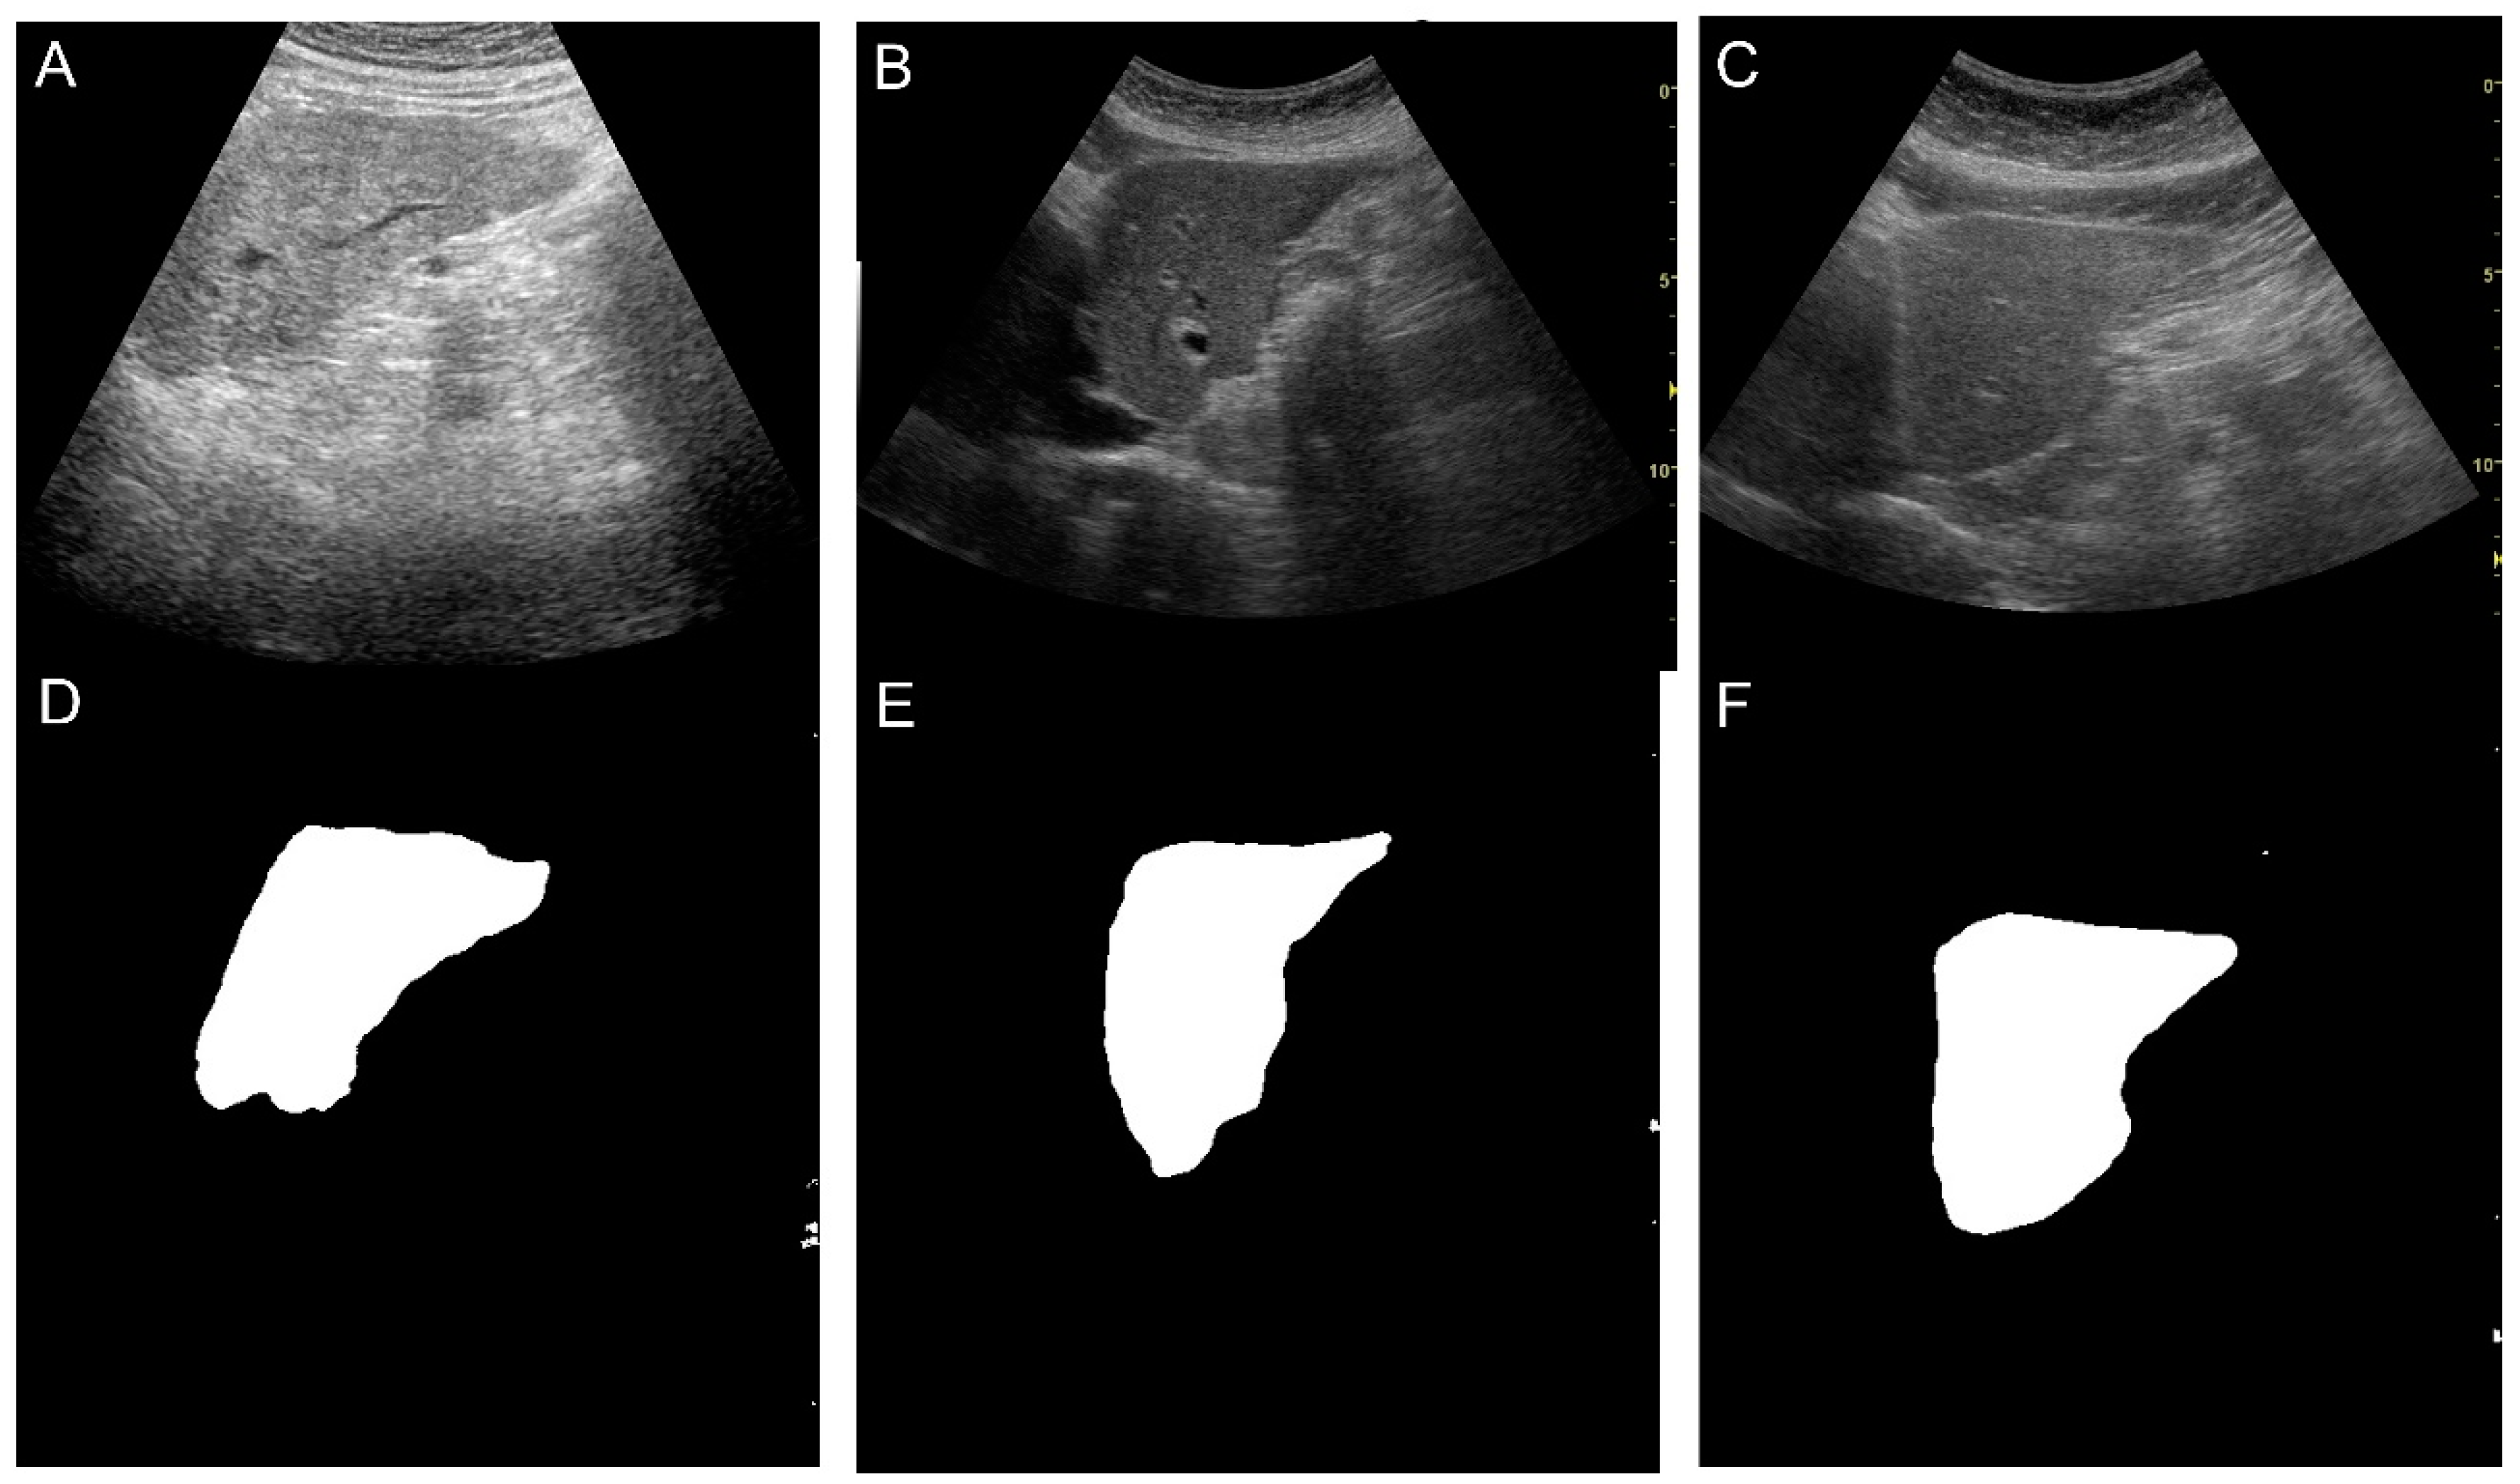

2.3. Image Pre-Processing and Machine Learning for Liver Segmentation

3.1. Accuracy of Liver Segmentation